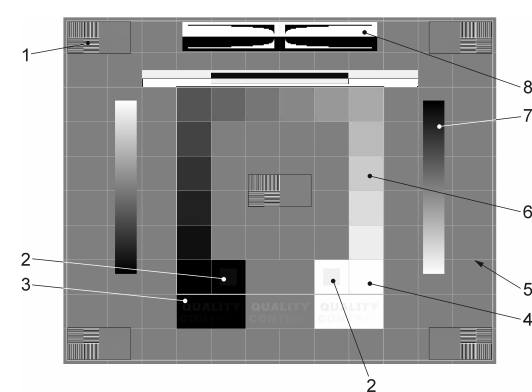

9.9. Konstanzprüfung

-

Prüfkriterien (Die Zahlen beziehen sich auf die Testbildelemente aus der DIN 6868-157).

-

Blenden Sie die Formularmaske aus. Diese kann jederzeit wieder aufgerufen werden (Tap auf das Testbild blendet Button mit Haken ein).

-

Markieren Sie das Kriterium mit dem Haken, falls die Bedingung erfüllt ist.

-

Speichern Sie die Durchführung und deren Ergebnisse ab.

-

Erhalten Sie mehr Informationen (öffnet das Handbuch, siehe nachfolgender Abschnitt).

Die Abbildung zeigt die einzelnen Testbildelemente. Folgende Punkte sind im Detail zu prüfen (nach Norm):

-

Sichtbarkeit der Linienpaar-Raster mit hohem KONTRAST in der Mitte und in den vier Ecken des TESTBILDES(Testbildelement 1)?

-

Sichtbarkeit der 5 %- und 95 %-Felder (Testbildelement 2)?

-

Qualitätskontrolle:

-

Im weißen und grauen Feld: „QUALITY CONTROL“ für alle Raumklassen

-

Im schwarzen Feld:

-

Mammographie:"QUALITY CONTROL".

-

RK1 (? 50 lx):"QUALITY CONTRO".

-

RK2 (? 100 lx):"QUALITY CONT".

-

RK3 (? 500 lx):"QUALITY CON" (test pattern element 3)?

-

-

-

Sichtbarkeit der Grenzen und Linien des Rasters und der Zentrierung des Rasters im aktiven Bereich des BILDWIEDERGABEGERÄTES(Testbildelement 5)?

-

Kontinuität des Erscheinungsbildes der Verlaufsbalken (Testbildelement 7)?